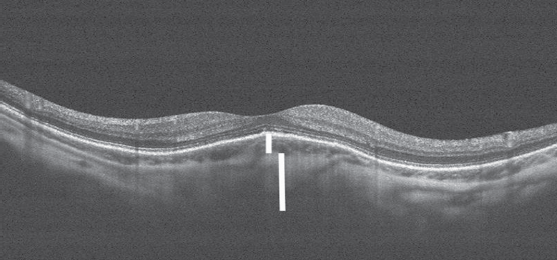

На поперечном срезе хорошо визуализируются наружные и внутренние слои сетчатки. Контрастная линия пигментного эпителия куполообразно приподнята, под ней виден неравномерный по толщине слой сосудов хориоидеи с выраженным утолщением склеры под ним. В то же время при типичной миопии высокой степени данные оптической когерентной томографии (ОКТ) выглядят иначе (рис. 2).

Рис. 2. Томограмма макулярной зоны сетчатки у пациентки с высокой миопией без куполообразной макулы (Optovue RTVue XR 100 Avanti). На томограмме линия пигметного эпителия ровная, нет приподнятости, под ней хориоидея и склера имеют равномерное строение, одинаковы по толщине на всём протяжении

На поперечном срезе линия пигметного эпителия ровная, нет приподнятости, под ней хориоидея и склера имеют равномерное строение, одинаковы по толщине на всём протяжении.